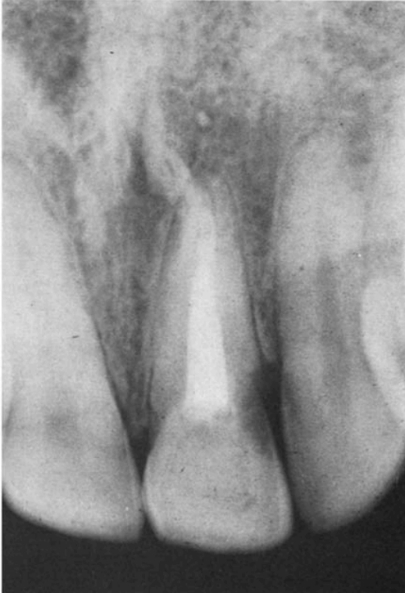

Пациент, девочка 14-лет впервые пришла на прием в 1966 году. Пульпа левого центрального резца верхней челюсти была травмирована в результате удара о дверь двумя неделями ранее (рис. 1). Эндодонтическое лечение было начато после осмотра в это же посещение и завершено через три недели (рис. 2).

Рисунок 1. — Клинический случай 1. Рентгенограмма левого центрального резца верхней челюсти, сделанная в 1966 году после травмы.